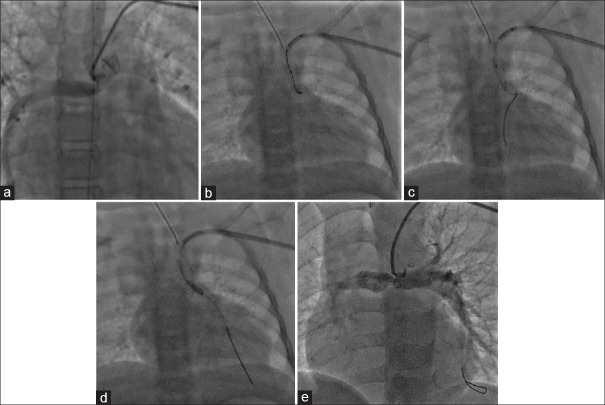

Balloon-assisted stent strut dilation in branch pulmonary artery stenosis following ductal stenting: An observation from tertiary care center in Eastern India.

导管支架置入术后肺动脉分支狭窄的球囊辅助支架支撑扩张:来自印度东部三级保健中心的观察。